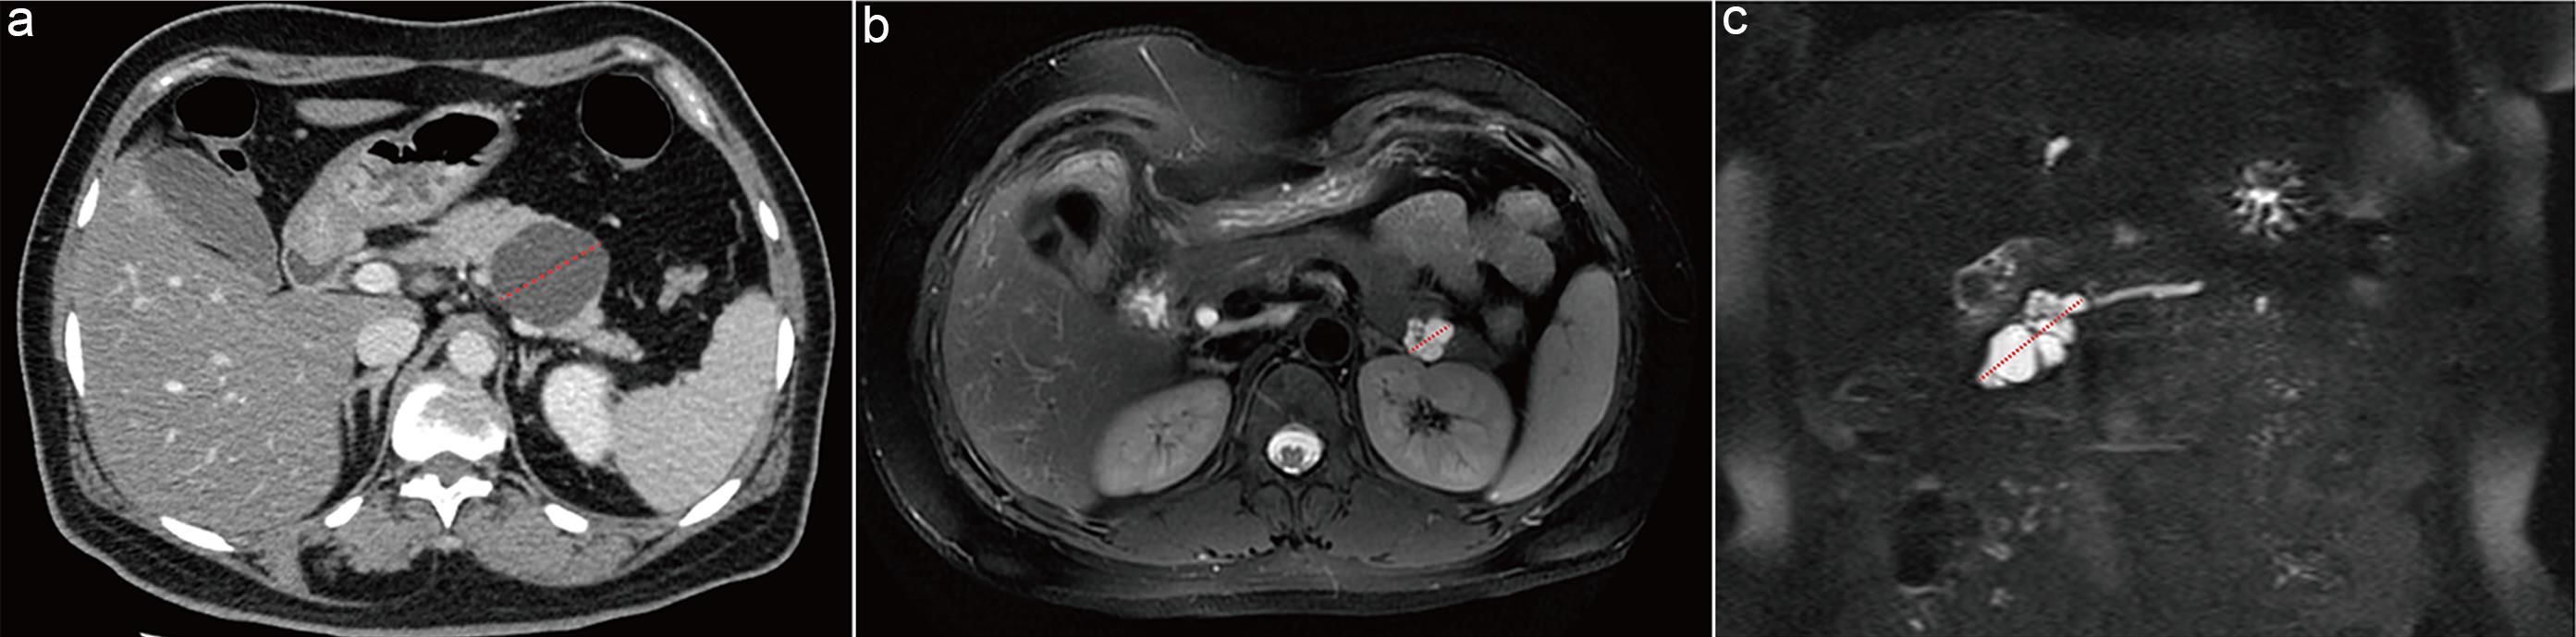

Previous studies have variably defined cyst wall or septal thickening as >2 mm or >3 mm.31,32 Due to inconsistent measurement methods among radiologists, interobserver agreement is poor.33,34 Therefore, this guideline adopts the evaluation standard from renal cystic tumors35: cyst wall or septal thickness >2 mm is considered thickened (Fig. 4a).

Assessment of cyst wall/septal thickening and communication with the main pancreatic duct.

Fig. 4  Assessment of cyst wall/septal thickening and communication with the main pancreatic duct.

(a) Mucinous cystic neoplasm in the pancreatic tail. Axial portal venous phase computed tomography (CT) image shows thickened internal septations within the cyst, with septal thickness >2 mm (arrow). (b) Branch-duct intraductal papillary mucinous neoplasm in the pancreatic head. Magnetic resonance cholangiopancreatography demonstrates communication between the cystic lesion and the main pancreatic duct (arrow).

Because cyst fluid and pancreatic juice in the main duct both appear hyperintense on T2WI and MRCP, these sequences facilitate visualization of their relationship (Fig. 4b).

Currently, there is no consensus on the measurement method for the main pancreatic duct. Based on existing literature,40–42 this guideline recommends measuring the maximal duct diameter on MRCP, T2WI, or contrast-enhanced CT during the pancreatic parenchymal or portal venous phase, selecting the plane perpendicular to the duct’s long axis (Fig. 5).

Methods for measuring the main pancreatic duct (MPD) diameter.

Fig. 5  Methods for measuring the main pancreatic duct (MPD) diameter.

(a) Main-duct intraductal papillary mucinous neoplasm (MD-IPMN). computed tomography (CT) curved planar reformation shows the optimal plane for measurement and the maximal diameter of the dilated MPD. (b) Main-duct IPMN. MR cholangiopancreatography (MRCP) shows measurement of the maximal diameter of the dilated MPD.